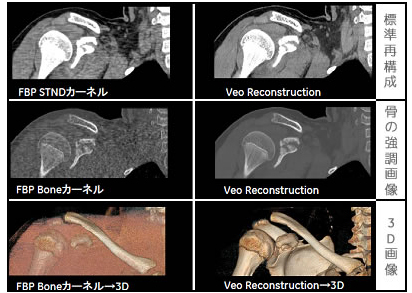

従来のCTでは,筋肉・臓器などの軟部組織や骨,肺といった検査する部位や組織ごとに撮影データを分け,異なる再構成関数にもとづいて,個別に画像を再構成する必要があった。Veoではこの関数の概念をCT画像再構成において初めてなくし,すべての部位・組織を1つの画像に集約する。再構成した画像はウインドのレベルとワイズ(コントラスト)の調整だけで,筋肉などの軟部組織から骨組織までクリアに描出可能。

再構成画像(左:Veo非搭載CT/右:Veo搭載CT)

通常のCTでは上記3画像を別々に再構成する必要があるが,Veoでは1回のみ